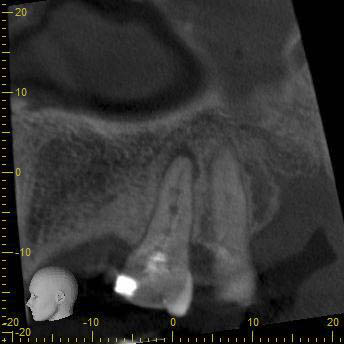

BN2627_DVT (2 von 17) Veröffentlicht 1. Dezember 2014 am 344 × 344 in Unerwartete Anatomie Zahn 26, 27- die WF